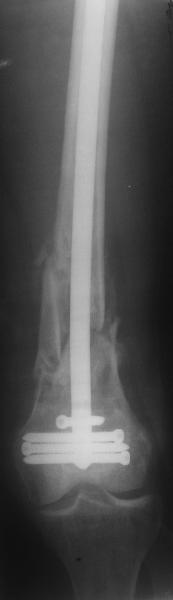

И вообще мне кажется, что представленный ОС не допустим:1. стержень в суставе,2. неправильная длинна винтов, 3. ось конечности неправильная, 4. циркулярная гипсовая повязка после ОС?????

-1. стержень в суставе,

Это не критично, в межмышелковой борозде,не на опроной поверхности, выступает из субхондральной кости, не факт что из хряща.Про надколенник Александр Николаевич уже писал.

-2. неправильная длинна винтов,

и толщина тоже. При такой длине хочется помощнее.

-3. ось конечности неправильная,

Вполне прилично. Если в боковой проекции рекувации нет. Где кстати боковая, хочется спросить у постмейкера.

- 4. циркулярная гипсовая повязка после ОС?????

К сожалению, автор умалчивает. Думается, что в данном случае можно и без гипса.

Приносим извенения за недостаток информации. Выкладываю все снимки. Стержень фирмы НПО ДЕОСТ(г.Пущино-на-оке)

|

Больная госпитализирована с тяжелой сочетанной травмой. Плюсом к перелому бедра имеется разрыв связок коленного сустава.